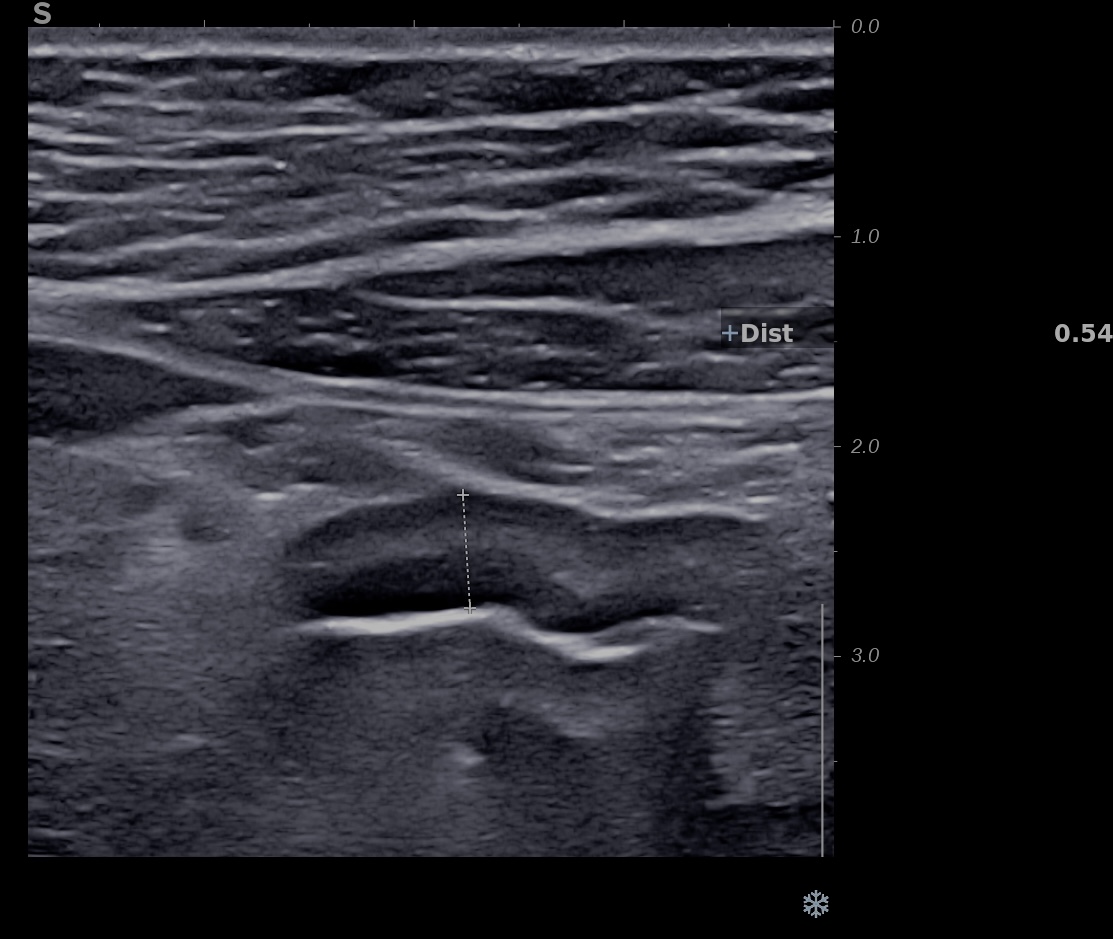

Patiente revue 4 ans plus tard sous vedolizumab Entiyo® en rémission clinique complète, biologie et calprotectine fécale normales, l’échographie (mauvaise échogénicité de la patiente) montre une paroi normalisée entre 1,8 et 2,8 mm d’épaisseur structure en couche conservée.

Le score de Milan MUC est à 3.92 confirmant la rémission échographique